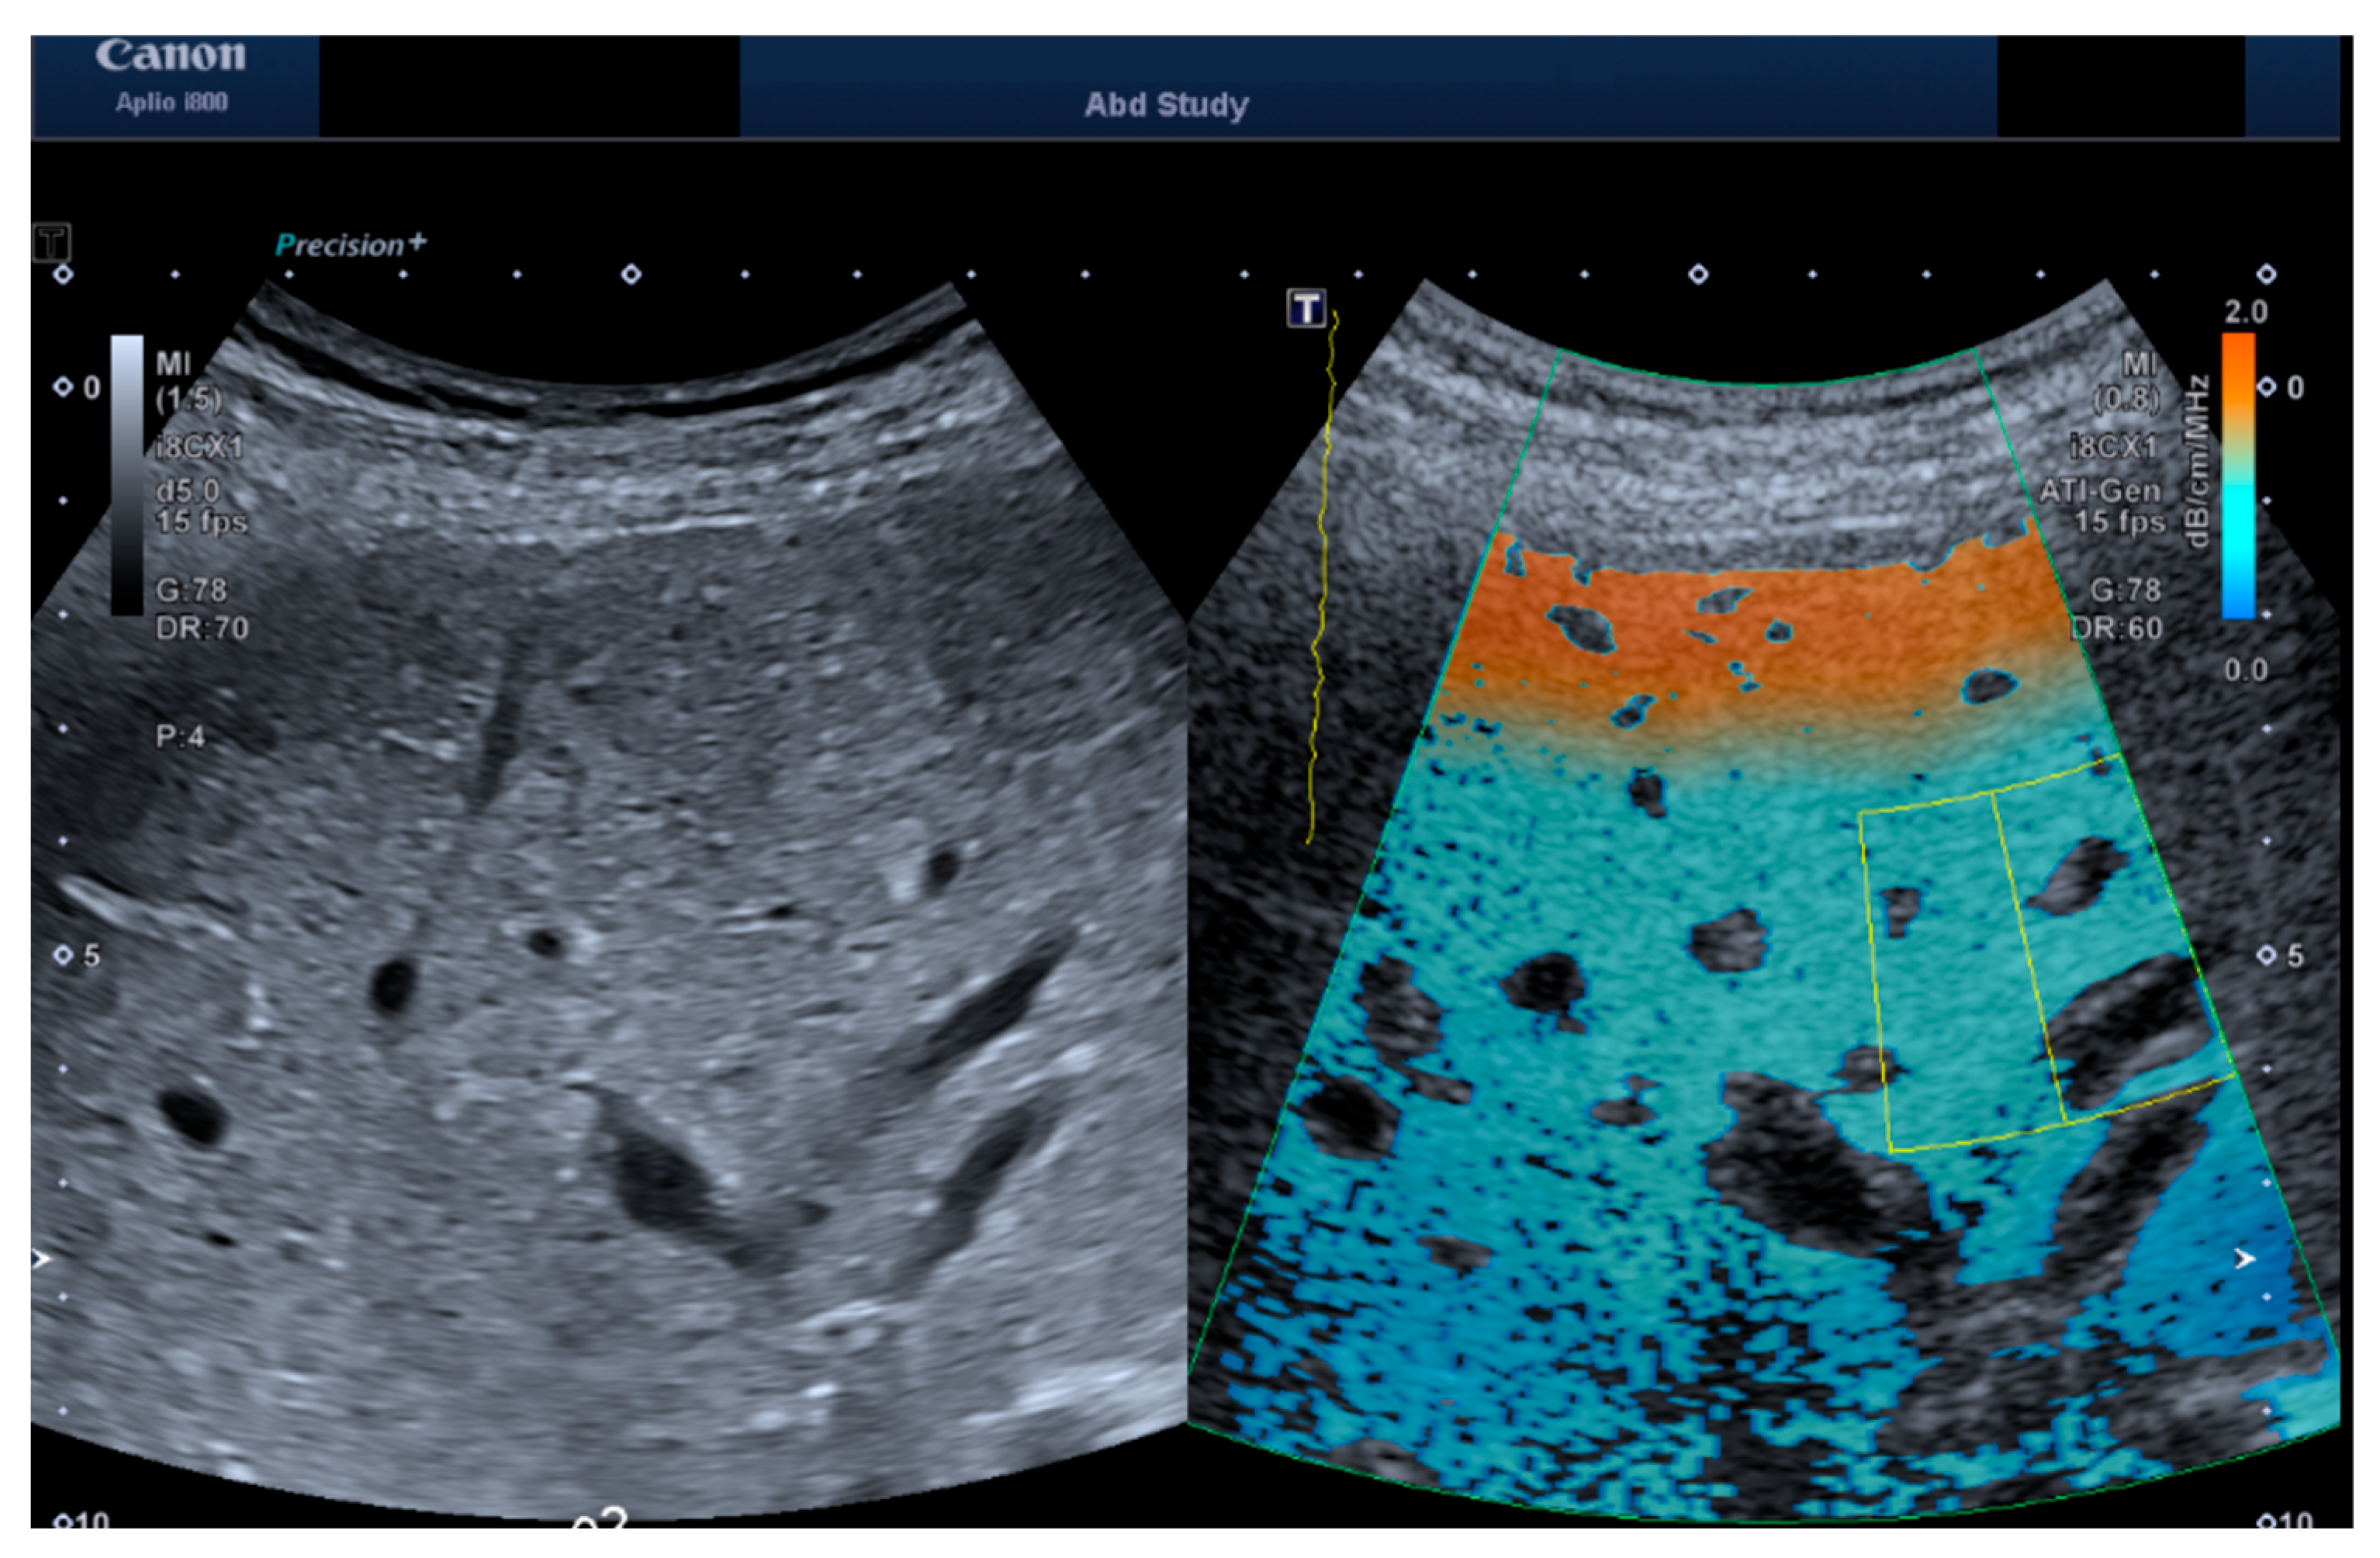

2.1. Measurement Protocol

2.2. Depth and ROI Size Analysis

2.3. HRI Versus Attenuation Coefficient